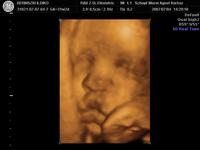

Szóval tegnap voltunk dokinál, méhszáj zárt, minden rendben, Máté pedig szép ütemben fejlődik. Óriásbaba nem lesz, de nem is baj, végülis valahogy elő is kell bújnia egy olyan kisebb kiszerelésű testből, mint az enyém. Ellenben rendezkedik odabent rendesen, meg feszít ezerrel. Élvezem nagyon, kivéve, mikor boxolja a hólyagomat. Meg van egy pont, amit mindig nyom, na az már kezd elég érzékennyé válni.

Aminek örülök: már több, mint 2 hete fejvégű. Remélem, így is marad. (Mellesleg lehet, hogy mégis forgolódik valahogy, mert elég amorf néha a pocim). Keményedések is vannak egyre sűrűbben, de általában csak 1-2 percig tartanak.